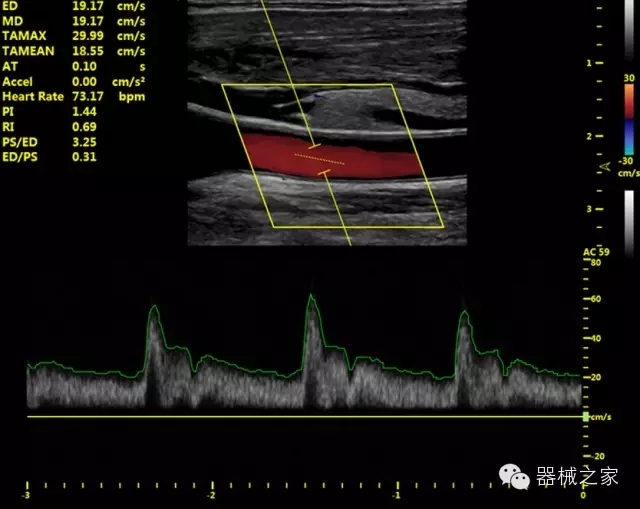

品牌:華聲醫(yī)療(WISONIC)

官方網(wǎng)站:www.wisonic.cn

經(jīng)典產(chǎn)品:四葉草

臨床圖片賞析

產(chǎn)品特點

·獨有的HoloTM PW 實時3取樣門PW成像技術(shù),精確進行血管診斷;

·一鍵優(yōu)化B、Color、PW,Auto Doppler自動識別血管位置、偏轉(zhuǎn)角度等,提高工作效率;

·30°超廣角精細偏轉(zhuǎn)成像技術(shù),更優(yōu)異的頻譜圖像;